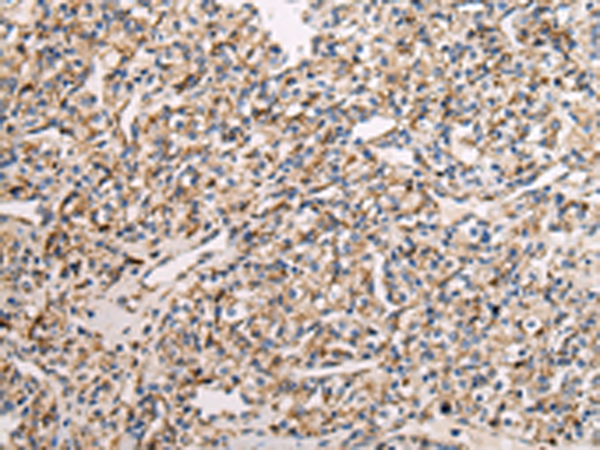

分类: 科研抗体货号: P08954别名: QCR2; UQCR2; MC3DN5应用: WB,IHC反应种属: Human, Mouse, Rat